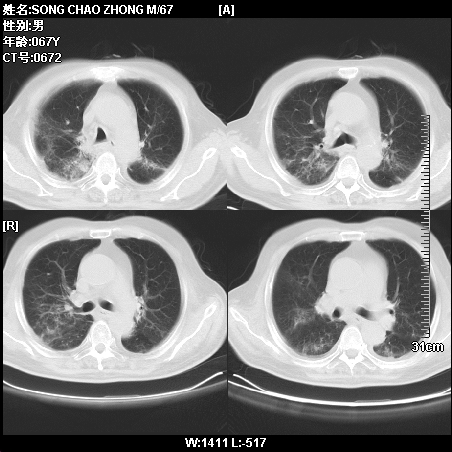

肿瘤科住院病人,都有食管癌史,都有放化疗治疗,两下肺病变是转移灶?还是其他原因造成?请老师指点

病例二 食管癌4个月,咳嗽咳痰,呼吸困难

第一个病例我感觉不是转移,第二个是个放射性肺炎;但两个都有纵隔淋巴结肿大,以第二个为主;请楼主参考

符合放射性肺炎,第一例不除外坠积效应